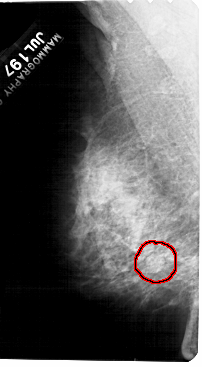

LEFT_MLO LINES 5491 PIXELS_PER_LINE 3016 BITS_PER_PIXEL 12 RESOLUTION 43.5 OVERLAY

FILE: A_1555_1.LEFT_MLO.OVERLAY

TOTAL_ABNORMALITIES 1

ABNORMALITY 1

LESION_TYPE MASS SHAPE ROUND MARGINS OBSCURED

ASSESSMENT 4

SUBTLETY 3

PATHOLOGY BENIGN

TOTAL_OUTLINES 1

BOUNDARY